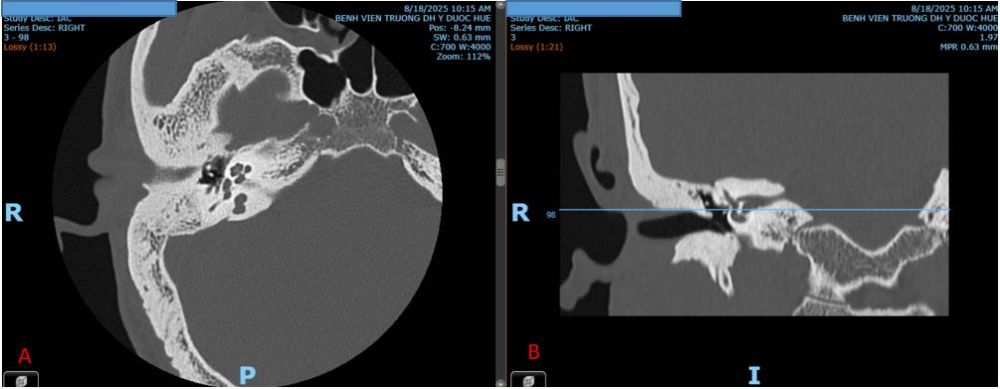

Tại Bệnh viện Đại học Y dược Huế vừa tiếp nhận điều trị một ca dị tật bẩm sinh đơn độc chuỗi xương con là một bệnh nhân nam 38 tuổi vào viện với tình trạng nghe kém từ nhỏ, tai bên trái nghe kém nặng hơn bên phải, tai ngoài và màng nhĩ bình thường. Thính lực đồ ghi nhận được sự gia tăng giá trị decibel (dB) đường khí ở hầu hết các tần số với trung bình đơn âm (PTA - Pure Tone audiogram)  tai trái 57,5 dB, tai phải gia tăng nhẹ 26,25 dB; Khoảng cách khí xương (ABG – Air born gap) tai trái 41.25 dB, tai phải 15 dB (Hình 1). Hình ảnh CTscan cho thấy tai trái: dị dạng cành xuống xương đe và xương bàn đap, xương búa hình dạng bình thường. Tai phải: cấu trúc chuỗi xương con bình thường (Hình 2).

Hình 2. Hình ảnh dị dạng chuỗi xương con tai trái trên CTscan.

Trên mặt phẳng Axial,tai trái cho thấy hình ảnh biến dạng xương bàn đạp, mất khoáng cửa sổ bầu dục (mũi tên màu cam). Trên mặt phẳng Coronal tai trái thấy hình ảnh dị dạng cành xuống xương đe (mũi tên màu đỏ).A,B. Tai phải; C,D. Tai trái